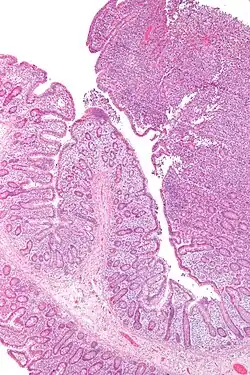

| Micrografia de um linfoma de células T associado a enteropatia (canto superior direito) | |

Linfoma de células T associado a enteropatia (EATL) é um tipo de linfoma das células T que afeta o intestino delgado. É o tipo mais comum de linfoma das células T gastrointestinais, partindo dos linfócitos T entre as células que revestem o intestino delgado.[1]